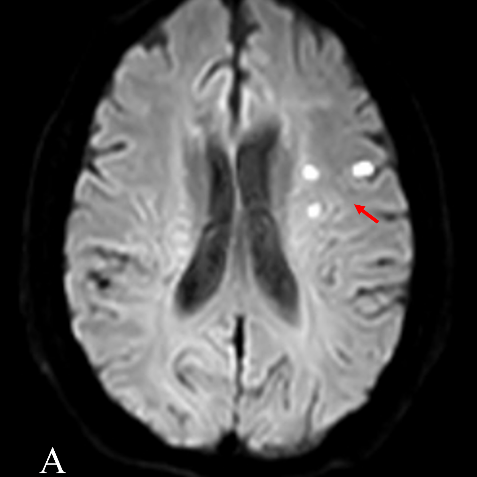

头颅MRI检查提示左侧额叶、放射冠及基底节区高信号(图A、B箭头所示);头颈CE-MRA显示右侧颈内动脉显影浅淡、断续显示、管径纤细,左侧颈内动脉闭塞,左侧椎动脉管径较对侧细,为非优势侧(图C箭头所示)。结合患者既往有脑梗死病史、2型糖尿病病史,本次脑梗死病因分型考虑为大动脉粥样硬化型,予以抗栓、他汀类药物治疗。问题来了,闭塞血管能否成功开通,代偿如何?

患者头颅MRI影像